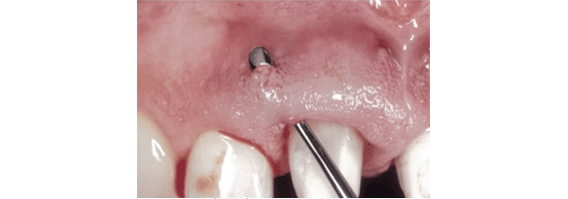

常采用间断或褥式缝合;悬吊缝合,多用于单侧翻瓣时使用。

对于美学区牙冠延长术,也可采用牙龈微创美容缝合,避免缝线暴露,达到美观、微创、加速愈合的效果。

间断缝合

术后两周拆线后口内情况